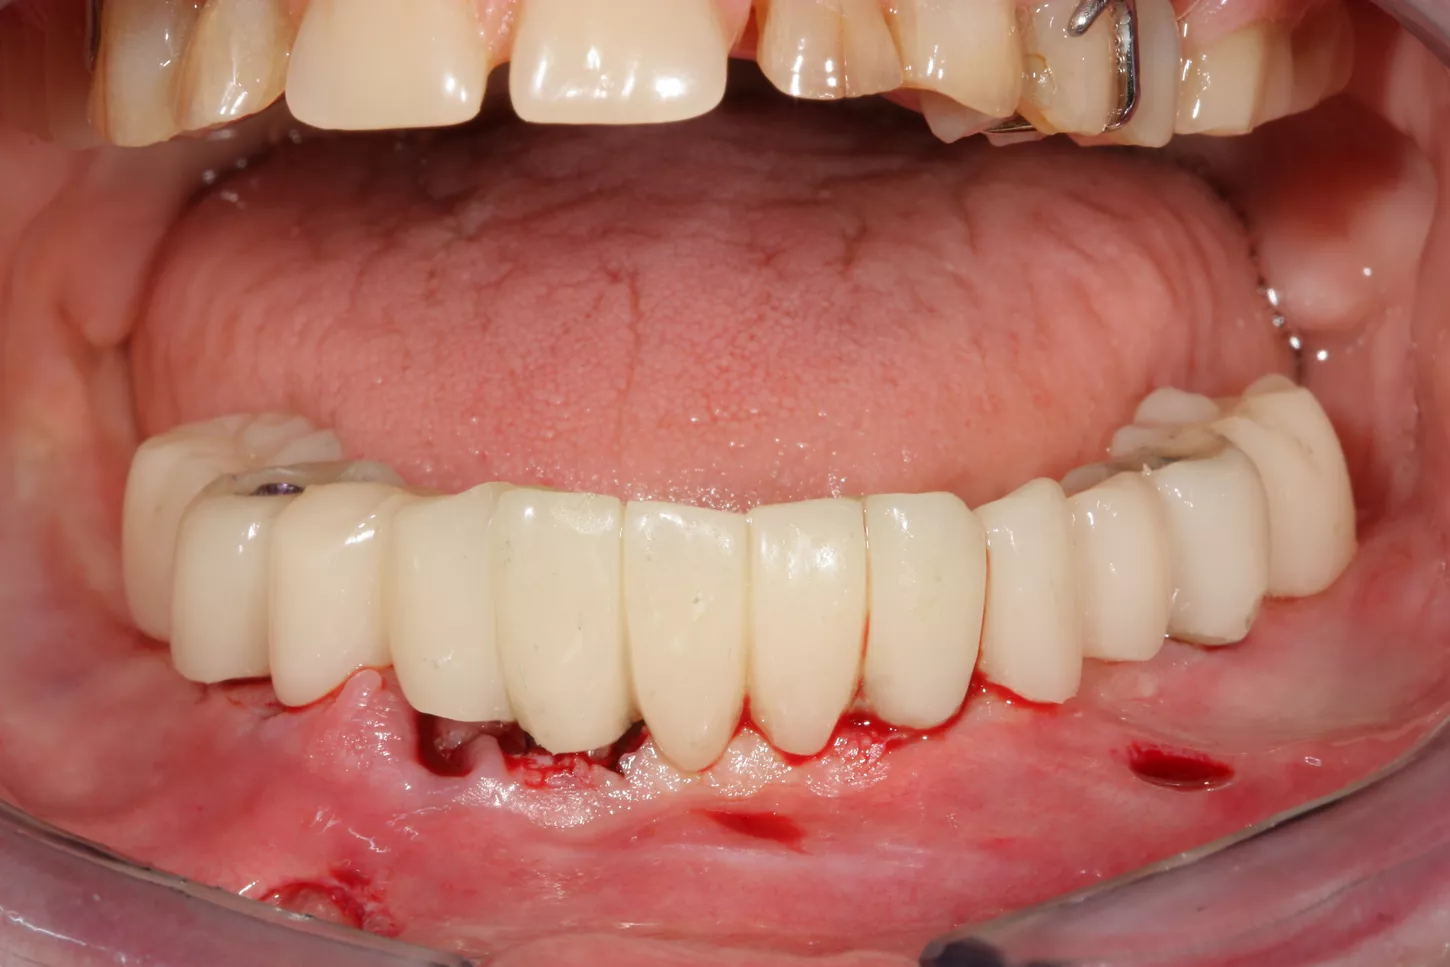

10.  The temporary restoration is positioned in the mouth using the final stackable splint to ensure that the patient's original occlusion is maintained. The temporary restoration is bonded intraorally around the temporary abutments. Despite the precise implant positioning, there may be slight deviations in the dental arch, so this procedure is recommended.

11. The temporary restoration with correct occlusion and jaw relation, at the end of the operation.

16. Display of the finished lower jaw work after osseointegration.